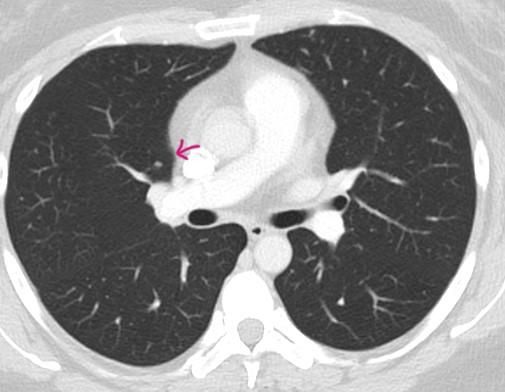

*좀더 하얀색인 사진 2장은 24년 조영제 폐CT 이고, 나머지 3장은 25년 저선량 CT사진입니다.

♧ 고형 같나요 간유리 같나요?

Ai 는 우상엽 solid라는데 오늘 2차병원에서 중간위치고 간유리에 가깝다라고 들어서요

solid nodule인지 ground glass nodule인지는 clear cut하게 나누어지는 것이 아닙니다. 결절이 색이 또렷하면 solid nodule인 것이고 흐지부지하면 ground glass nodule인 것입니다. 이건 육안 소견을 두고 말하는 것입니다. 따라서 일부 nodule에 있어서는 판독하는 의사에 따라 소견이 다를 수 있습니다.